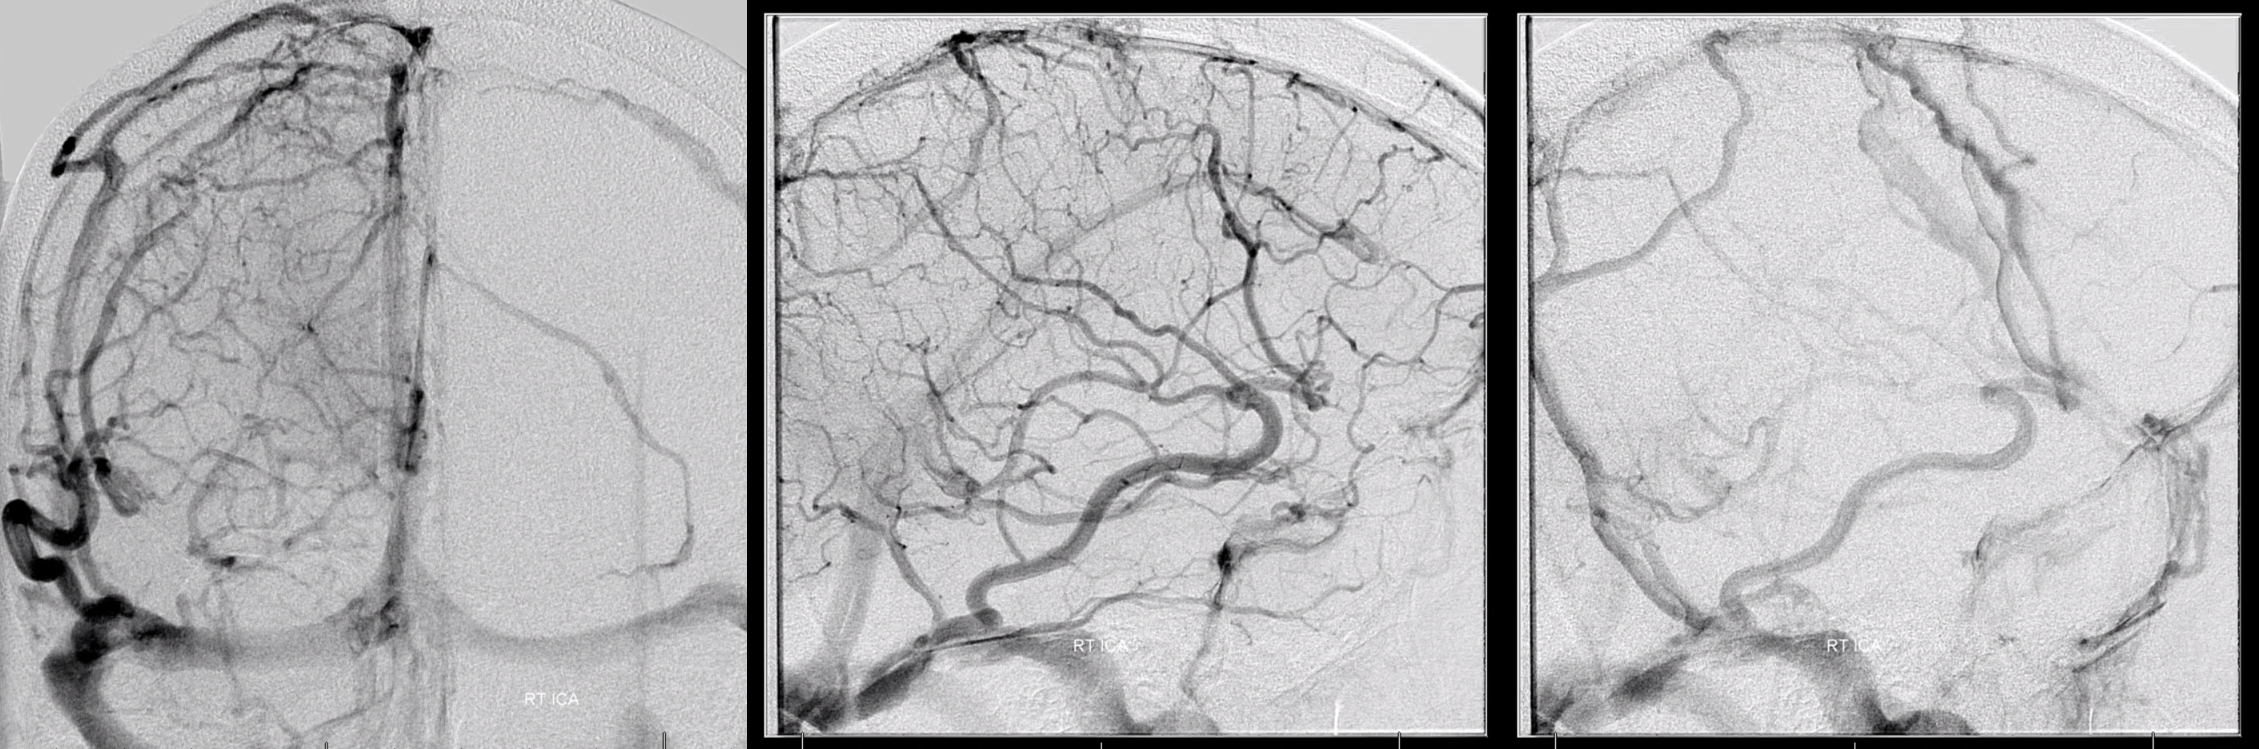

Below is a case of severe venous sinus thrombosis and secondary parenchymal venous infarcts

The explanation for the above tragic pattern is below. On the right, sigmoid and transverse sinuses are patent. However, the Labbe is hypoplastic, and majority of outflow used to go to the Trolard, into the now occluded SSS. There is no other effective way to go — the trolard tries to decompress via a left diploic vein, and convexity tries to access the deep venous system (which normally should not be well-seen in setting of hypoplastic right A1 segment). The left situation is much better, as well-developed superficial sylvian veins drain into the patent Cavernous Sinus. Thus, despite thrombosis of the left transverse and sigmoid sinuses, the left hemisphere is doing better, while the right one, which has patent transverse and sigmoid sinuses, is devastated.

Post venous thrombectomy — with limited results. Note presence of same left diploic vein as seen in right ICA injection, and connection between the distal superior sagittal sinus and the deep venous system via the inferior sagittal sinus.

All of the above anatomic knowledge can become very useful in evaluation of venous thrombosis. Numerous collateral pathways develop in this setting attempting to compensate for the loss. The most dramatic cases usually involve the largest channel — the superior sagittal sinus. In this case, a man presented with what initially was thought to be vasculitis-related brain hemorrhage. Subsequent workup led to an angiogram, where sagittal sinus thrombosis with extensive trans-cerebral and trans-osseous emissary vein collateral channels was seen. In retrospect, these findings were present on the patient’s earlier contrast MRI. “Venovibe” or other contrast-enhanced MR venograms can very sensitive, particularly when interpreted with the appropriate index of suspicion. Noncontrast 2-D time of flight MRV I consider to be next to useless as a problem-solving technique. Any thin-slice postcontrast T1 study is vastly superior.